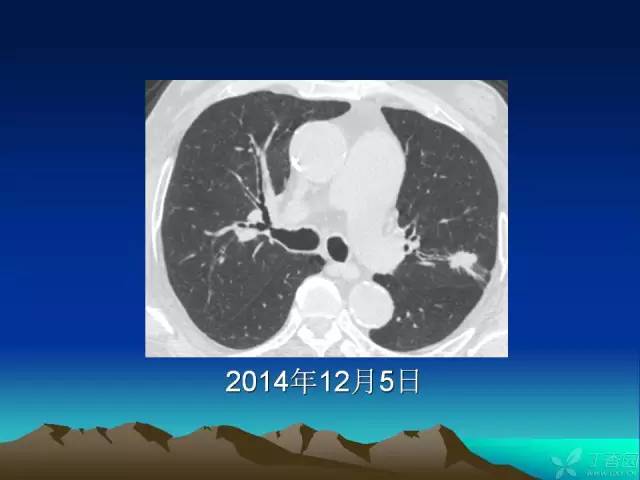

【PPT】早期肺癌易漏诊征象分析